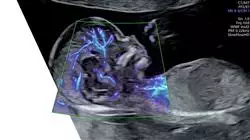

Die fetale Echokardiographie ist ein wichtiges Instrument für die Frühdiagnose angeborener Herzanomalien beim Fetus, das ein frühzeitiges Eingreifen ermöglicht und die Prognose der Patienten verbessert. So steht dieser Bereich vor besonderen Herausforderungen, wie z. B. der Notwendigkeit, immer komplexere Pathologien zu erkennen und zu behandeln, und das in einem Umfeld, in dem sich die Technologie ständig weiterentwickelt.

Vor diesem Hintergrund wird der Universitätskurs in Fetale Angeborene Herzfehler vorgestellt, der sich auf einen vollständigen Lehrplan stützt, der vom fetalen Kreislauf über die Untersuchung der fetalen Herzfunktion bis hin zu fetalen Herzrhythmusstörungen alles umfasst. Dieses Programm soll das Wissen von Ärzten und Spezialisten auf den neuesten Stand bringen und ihnen einen umfassenden und aktuellen Überblick über die Techniken der fetalen Echokardiographie zur Erkennung angeborener Herzfehler geben.